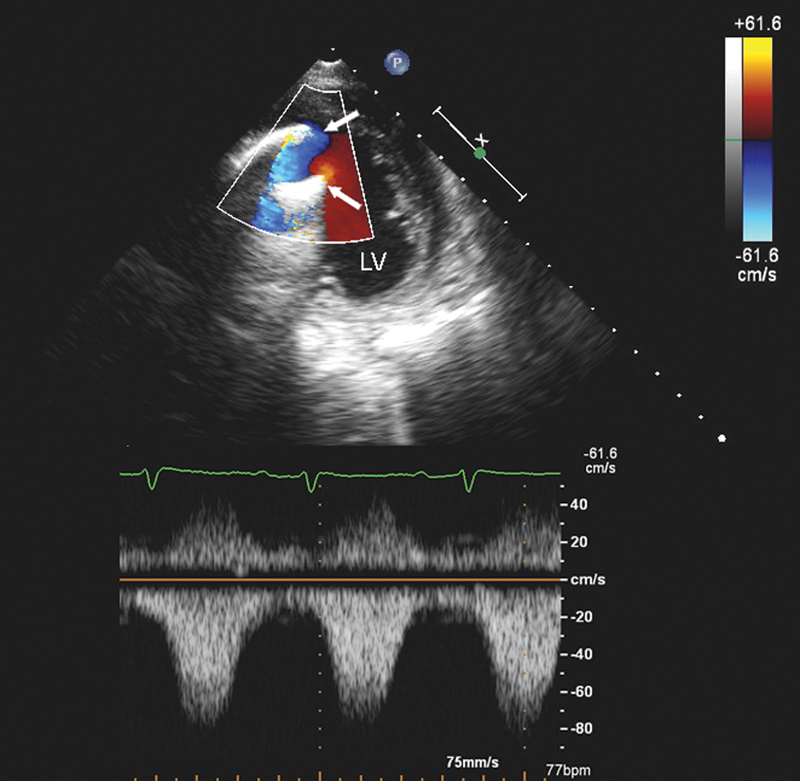

فحوصات تشخيصية لبعض امراض القلب والشرايين التاجية